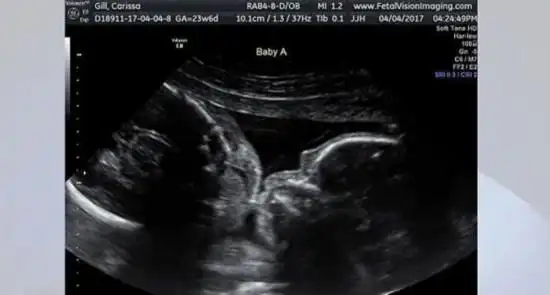

彩超显示美双胞胎在妈妈肚子里甜蜜亲吻